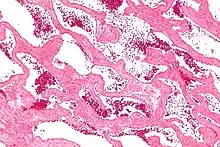

Micrograph of a cavernous liver hemangioma. H&E stain.